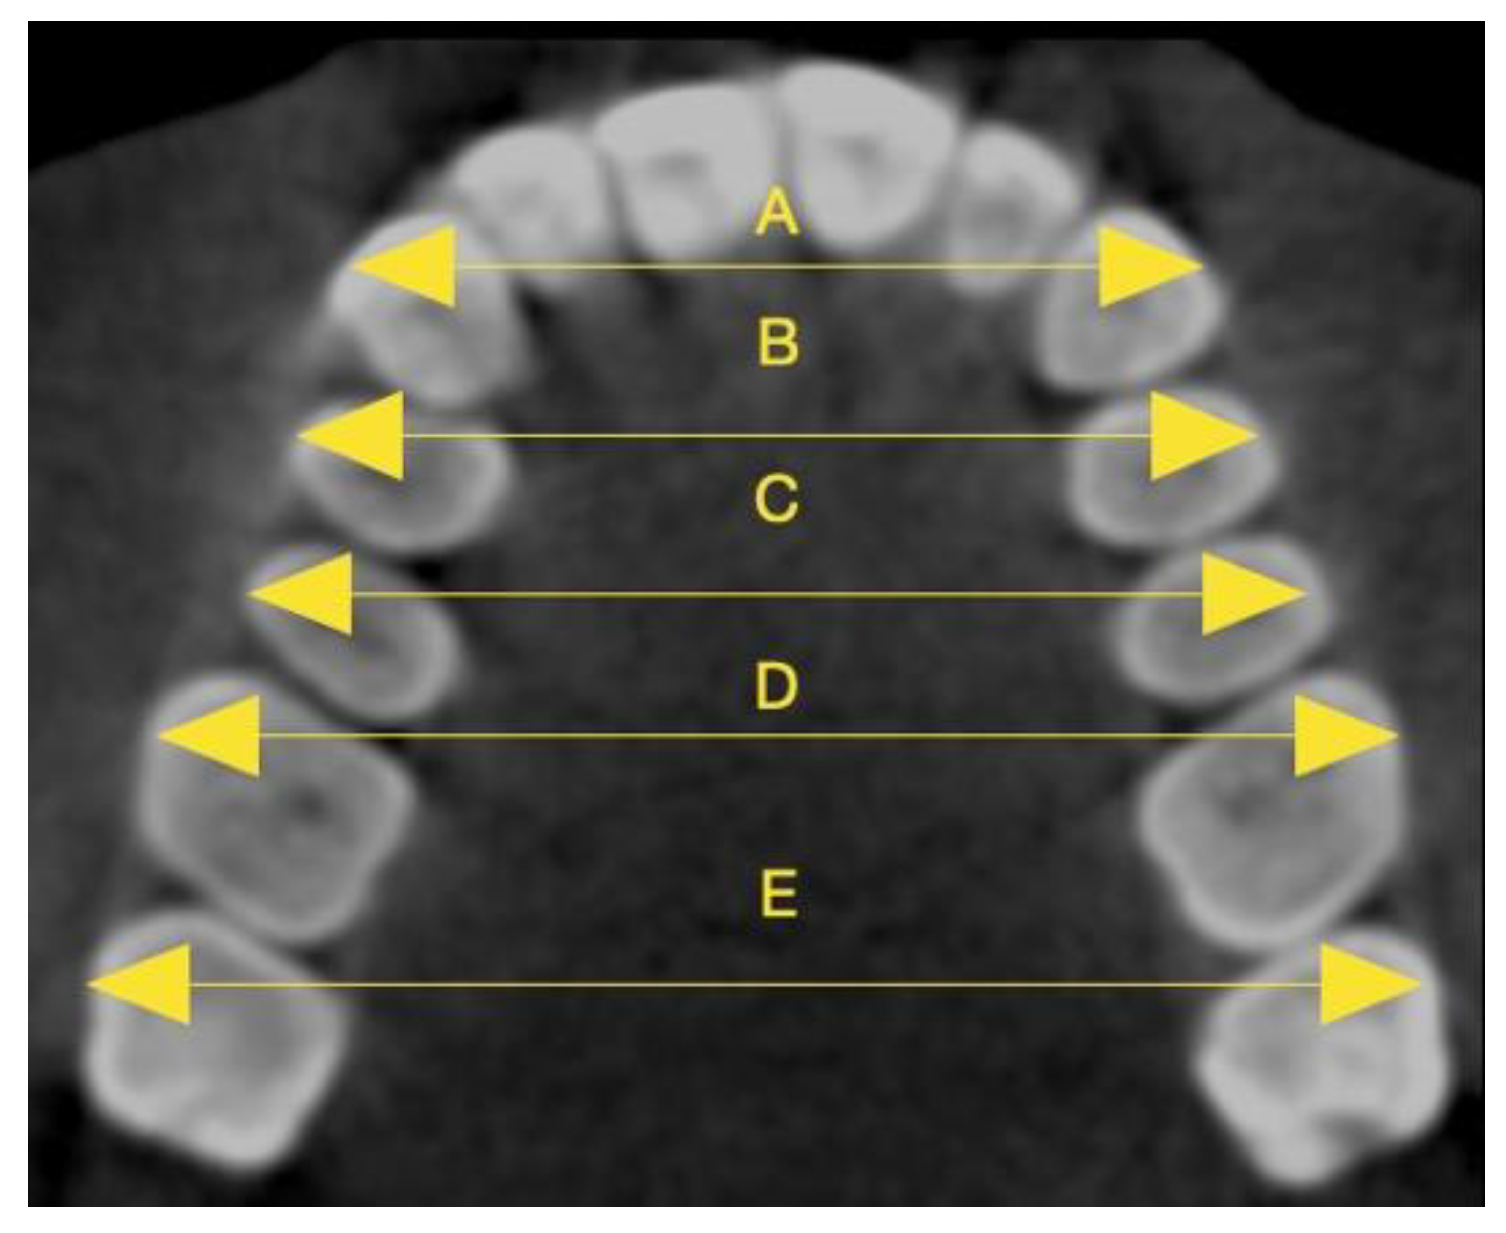

| Inter-Apex Width | T1-T0 (mm) (Mean ± SD) | T1-T0 Minimum–Maximum Values (mm) | T1-T0 (%) (Mean ± SD) | T1-T0 Minimum–Maximum Values (%) | p-Value |

|---|---|---|---|---|---|

| Intercanine | 1.31 ± 0.73 | 0.10–2.50 | 4.39 ± 2.43 | 0.34–8.39 | 5.84596 × 10−17 ** |

| First interpremolar | 1.89 ± 0.39 | 0.7–2.6 | 5.18 ± 1.11 | 1.93–7.22 | 1.07006 × 10−35 ** |

| Second interpremolar | 1.48 ± 0.68 | 0.10–2.60 | 3.53 ± 1.63 | 0.24–6.15 | 2.33339 × 10−20 ** |

| First intermolar | 0.70 ± 0.26 | 0.10–1.20 | 1.40 ± 0.53 | 0.20–2.41 | 4.20634 × 10−24 ** |

| Second intermolar | 0.15 ± 0.09 | 0–0.40 | 0.29 ± 0.17 | 0–0.77 | 2.28014 × 10−16 ** |